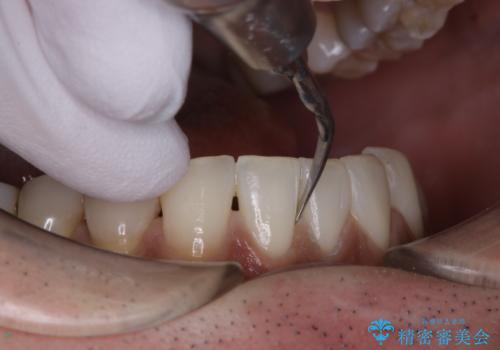

60分のPMTCで歯の黄ばみをきれいに除去

- 年末年始と忙しく、なかなか歯のケアがしっかりできなかった事と着色も気になるとのことで来院されました。PMTC60分コースを行いました。